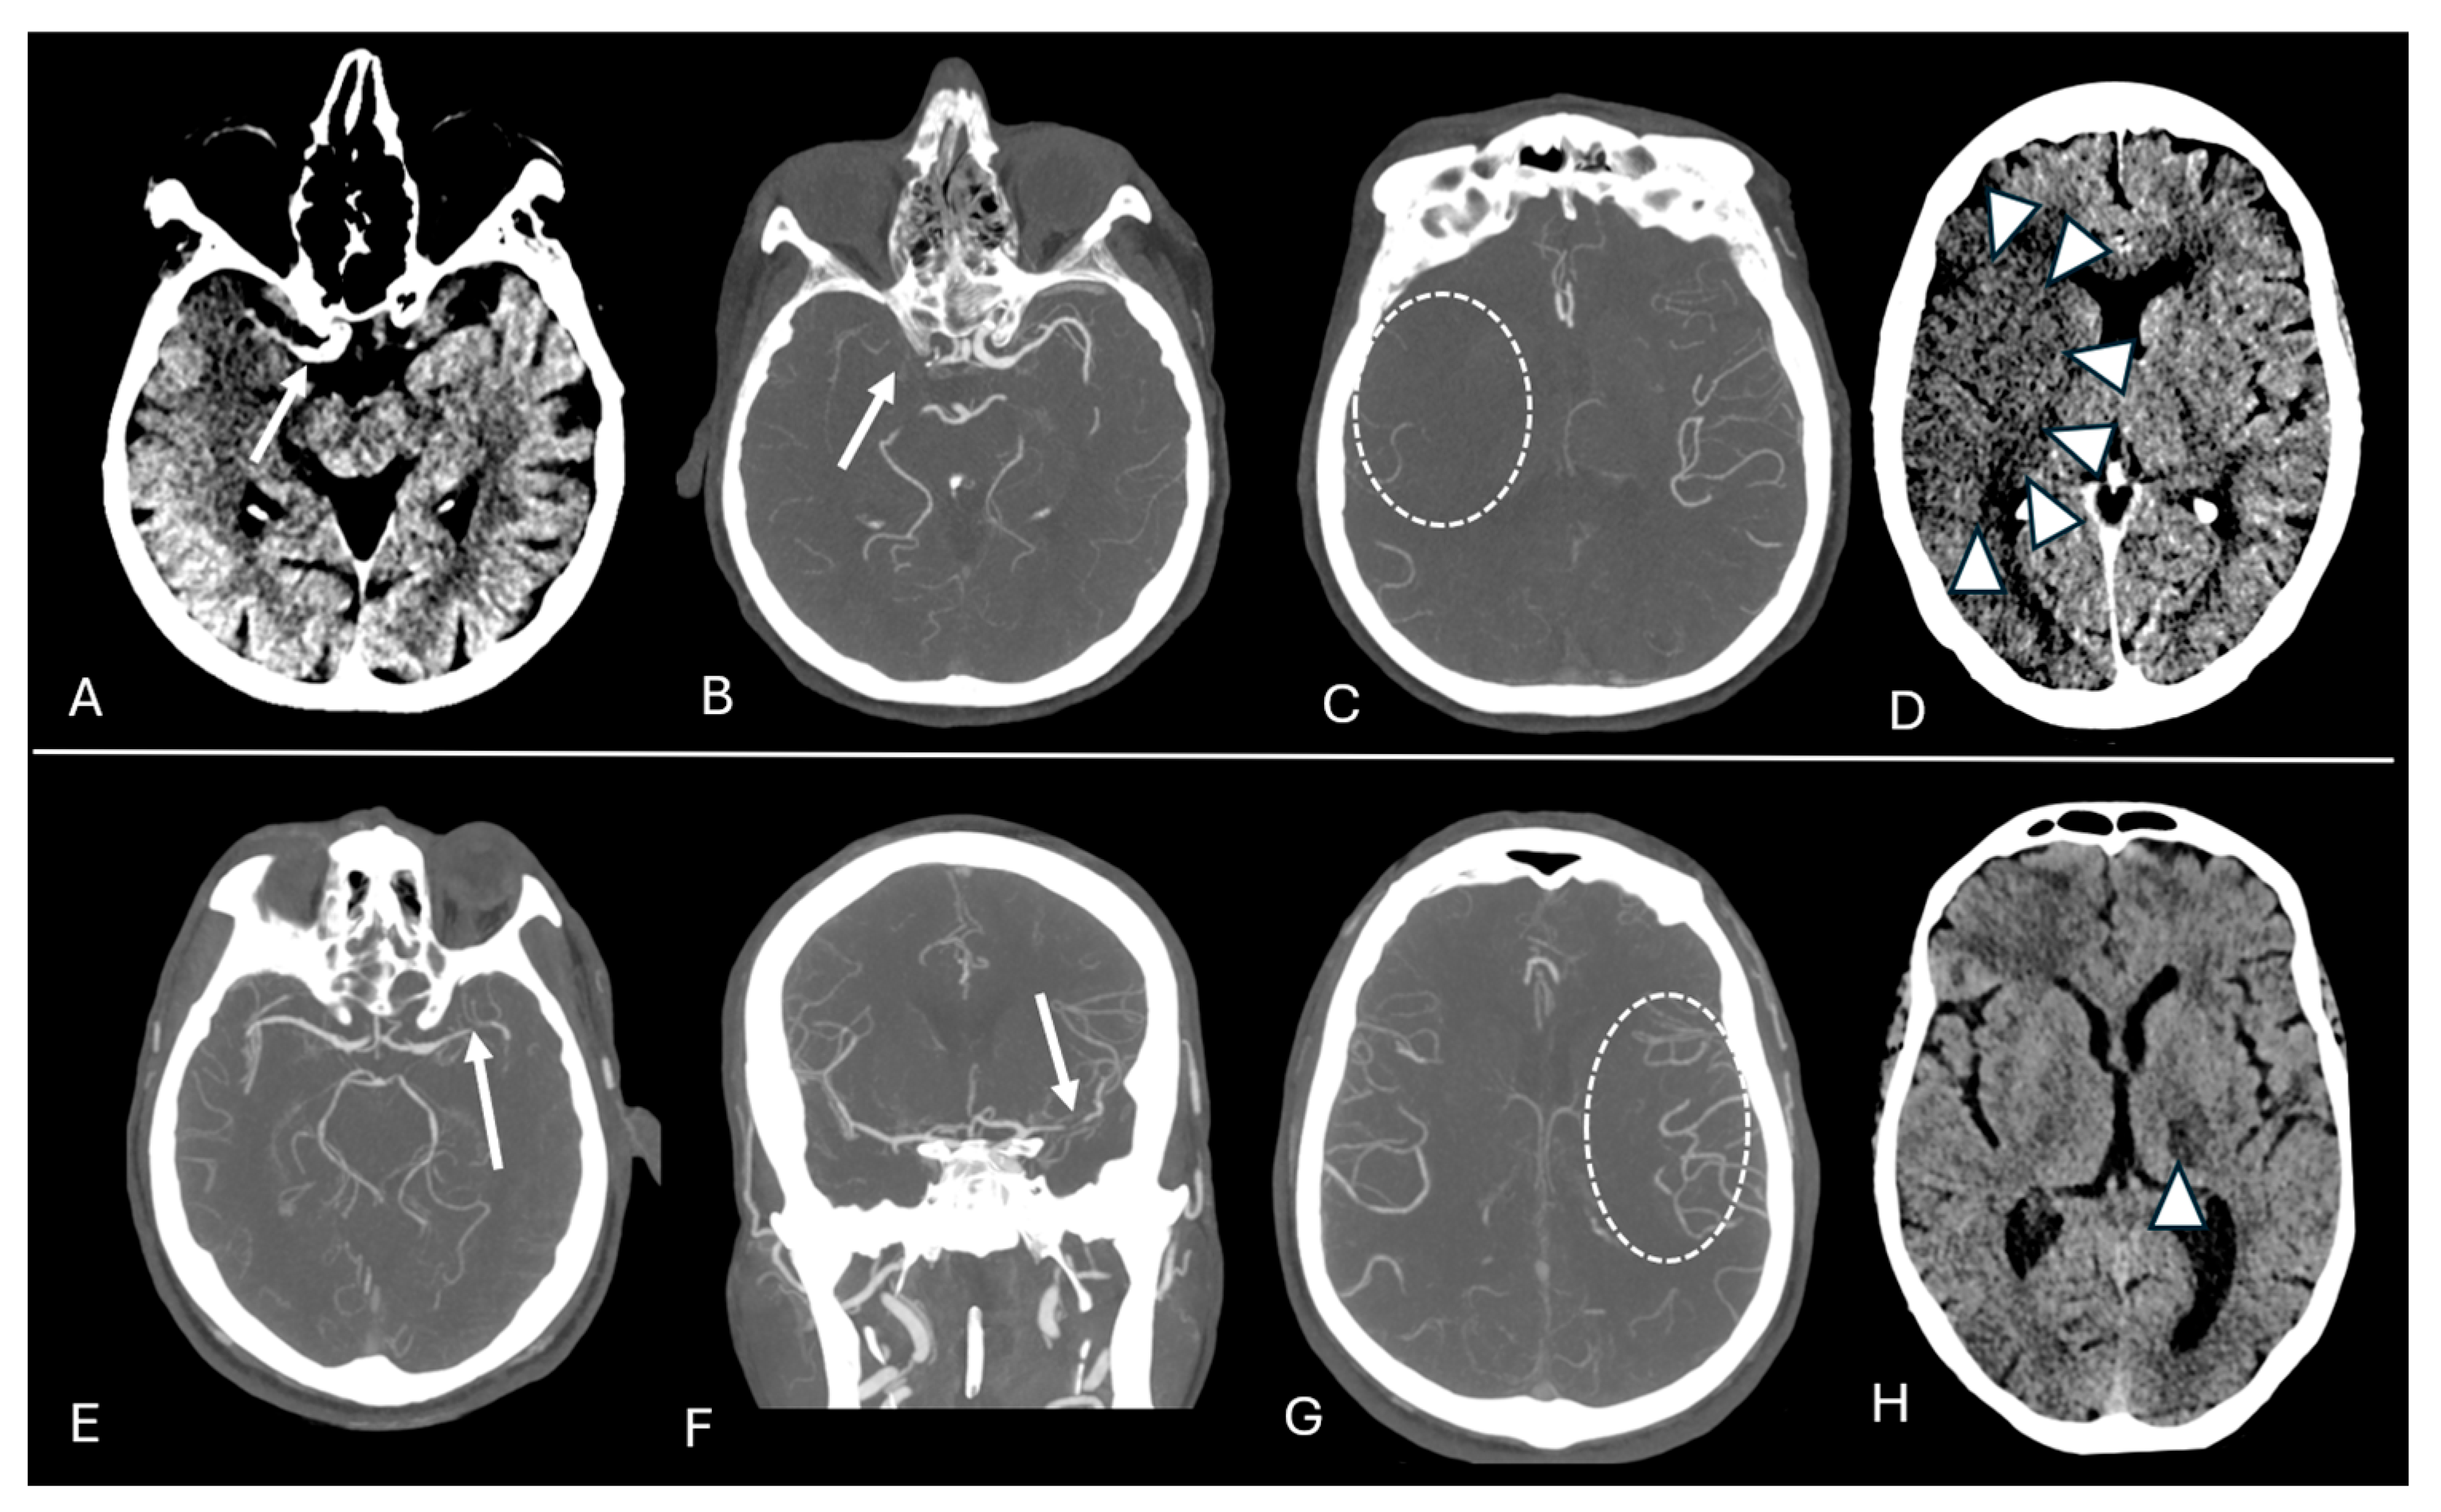

2.2. Imaging Protocol and Analyses

3. Results

3.2. Outcome Analyses

4. Discussion